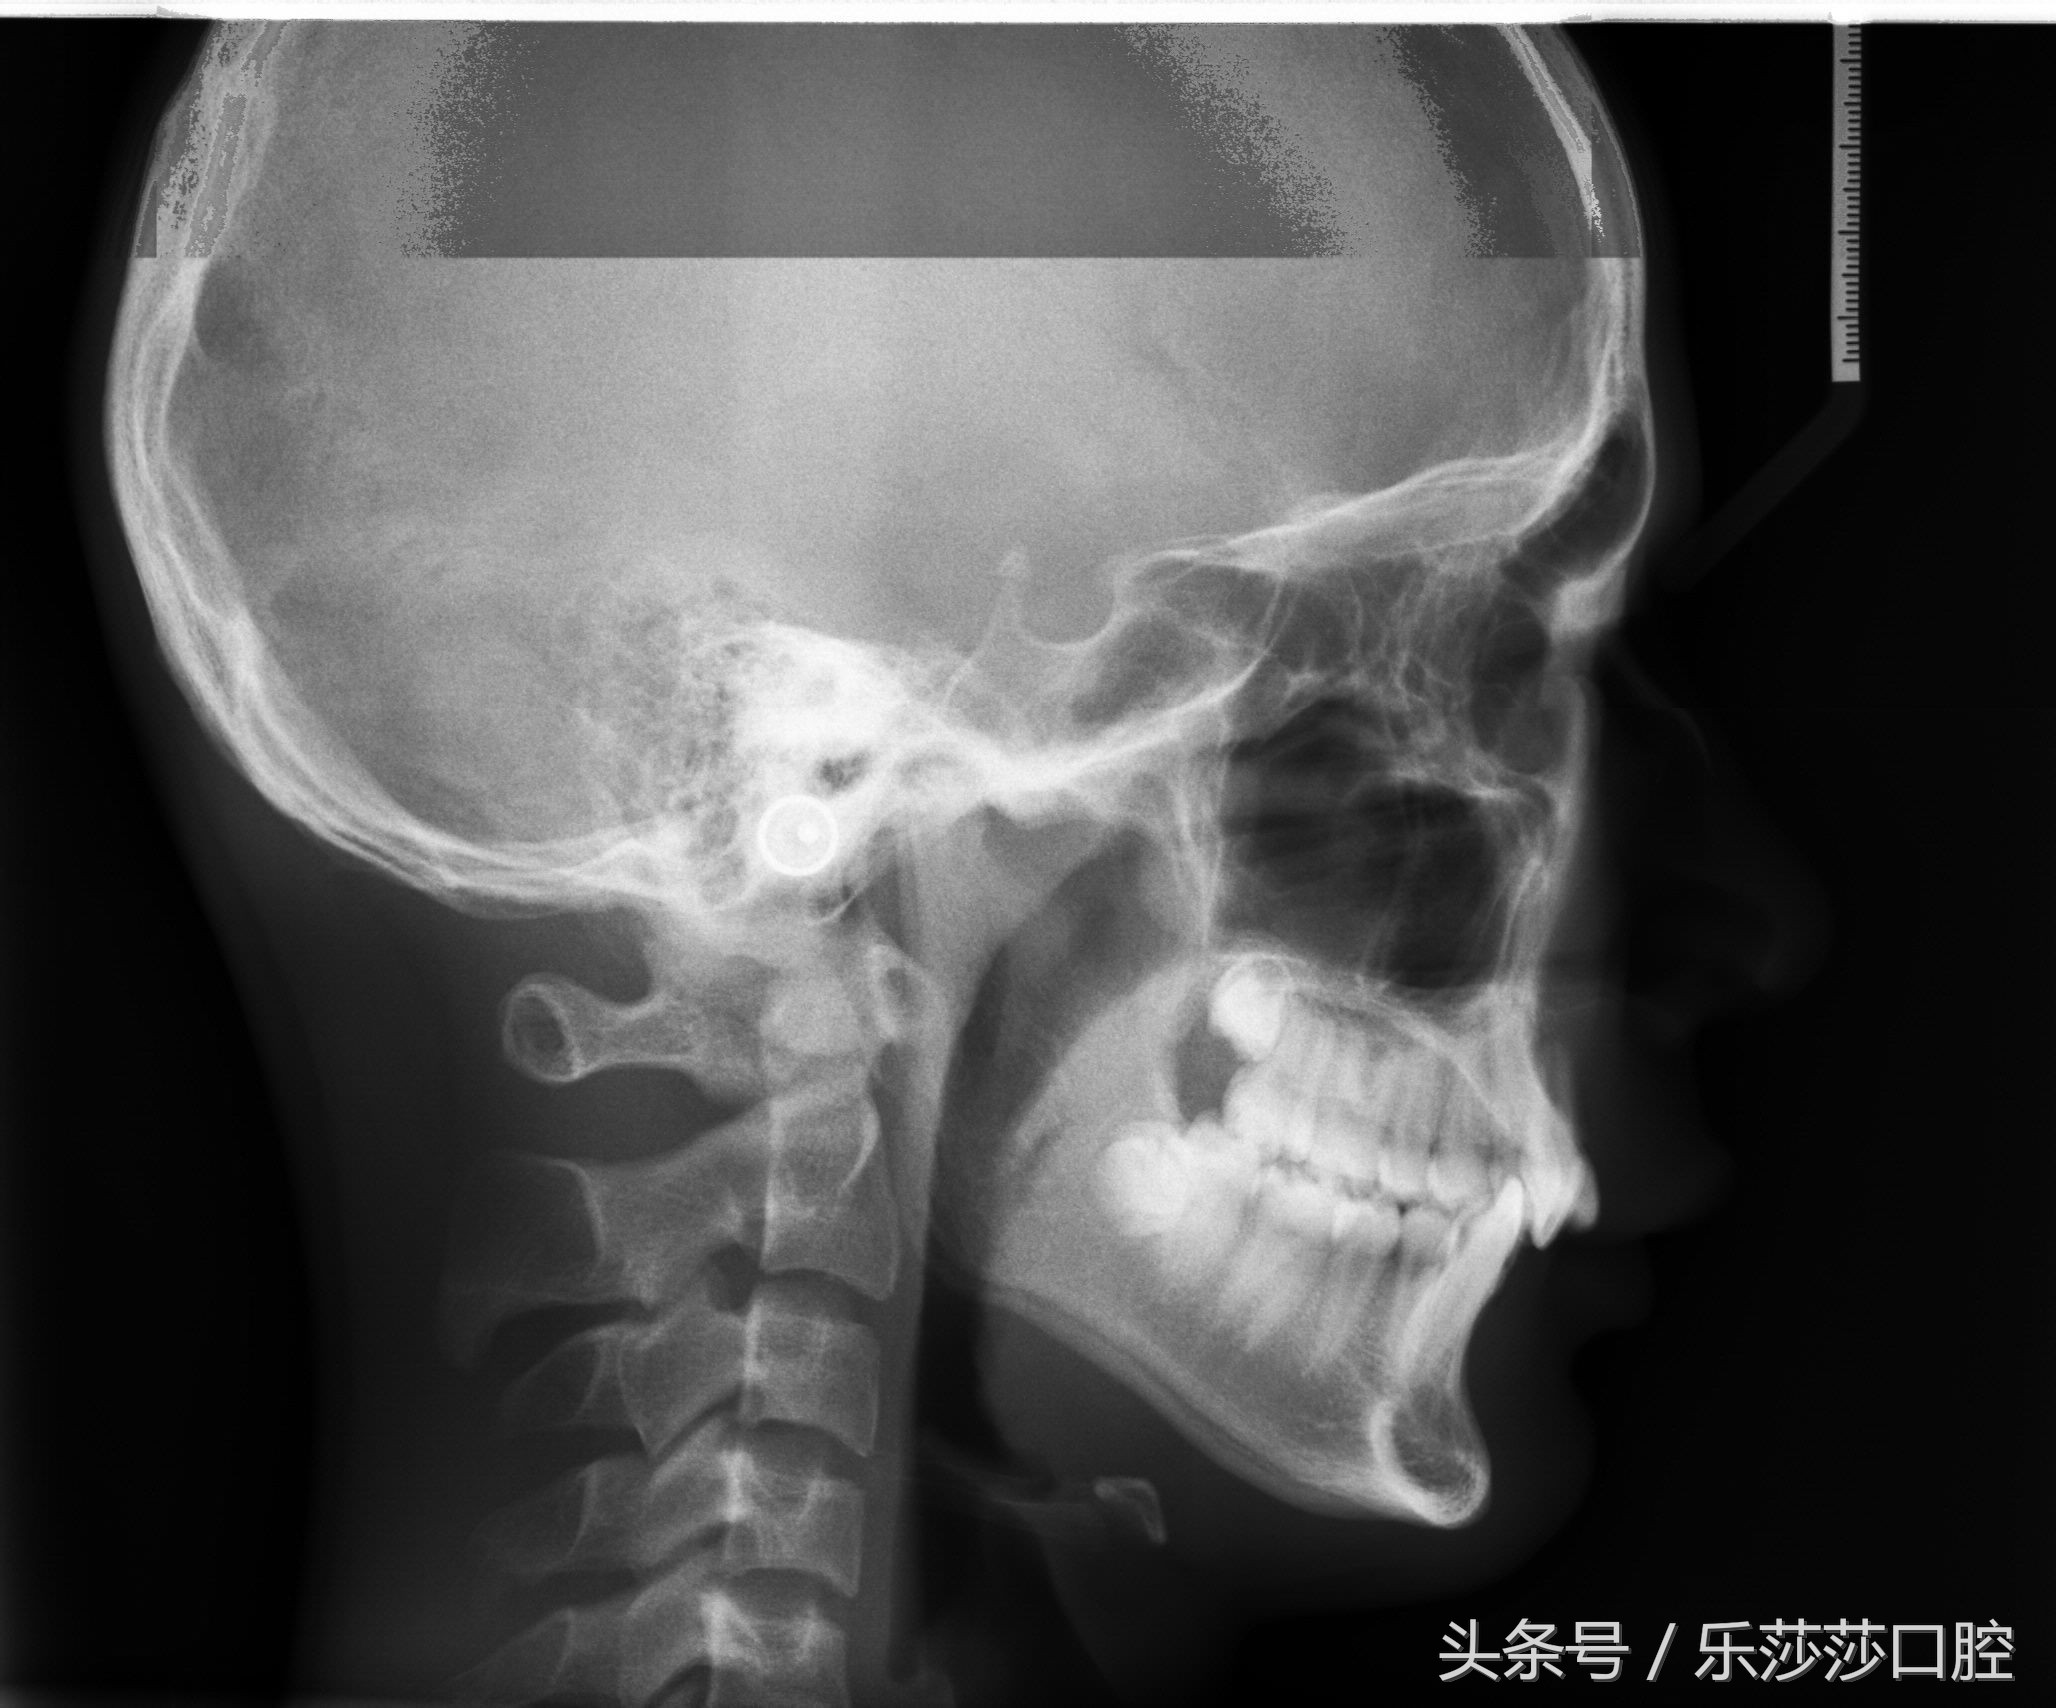

3)拍片,取模:是整牙过程中不可缺少的一部分,目的是了解牙齿具体情况,有无埋伏牙,有无异常发育牙齿,牙根形态、位置,有无吸收等情况。分析完后牙医会给你列出几种牙齿矫正的解决方案让你选择。